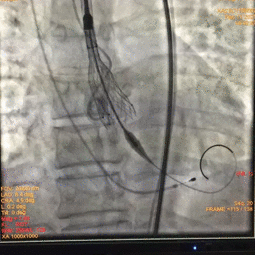

术中影像

图片

根部造影

球囊预扩

瓣膜释放至2/3造影观察

瓣膜释放后形态欠佳

经球囊后扩后瓣膜形态良好

手术结果

术后造影及超声探查未见瓣周漏,跨瓣压差术前183mmHg,术后几乎无压差,术中及术后未出现相关并发症,手术圆满完成。